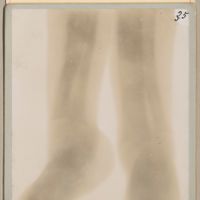

0063 - Page 35 - 29 mars. - Jambes et talons rachitiques / 20 minutes de pose0063 - Page 35 - 29 mars. - Jambes et talons rachitiques / 20 minutes de pose